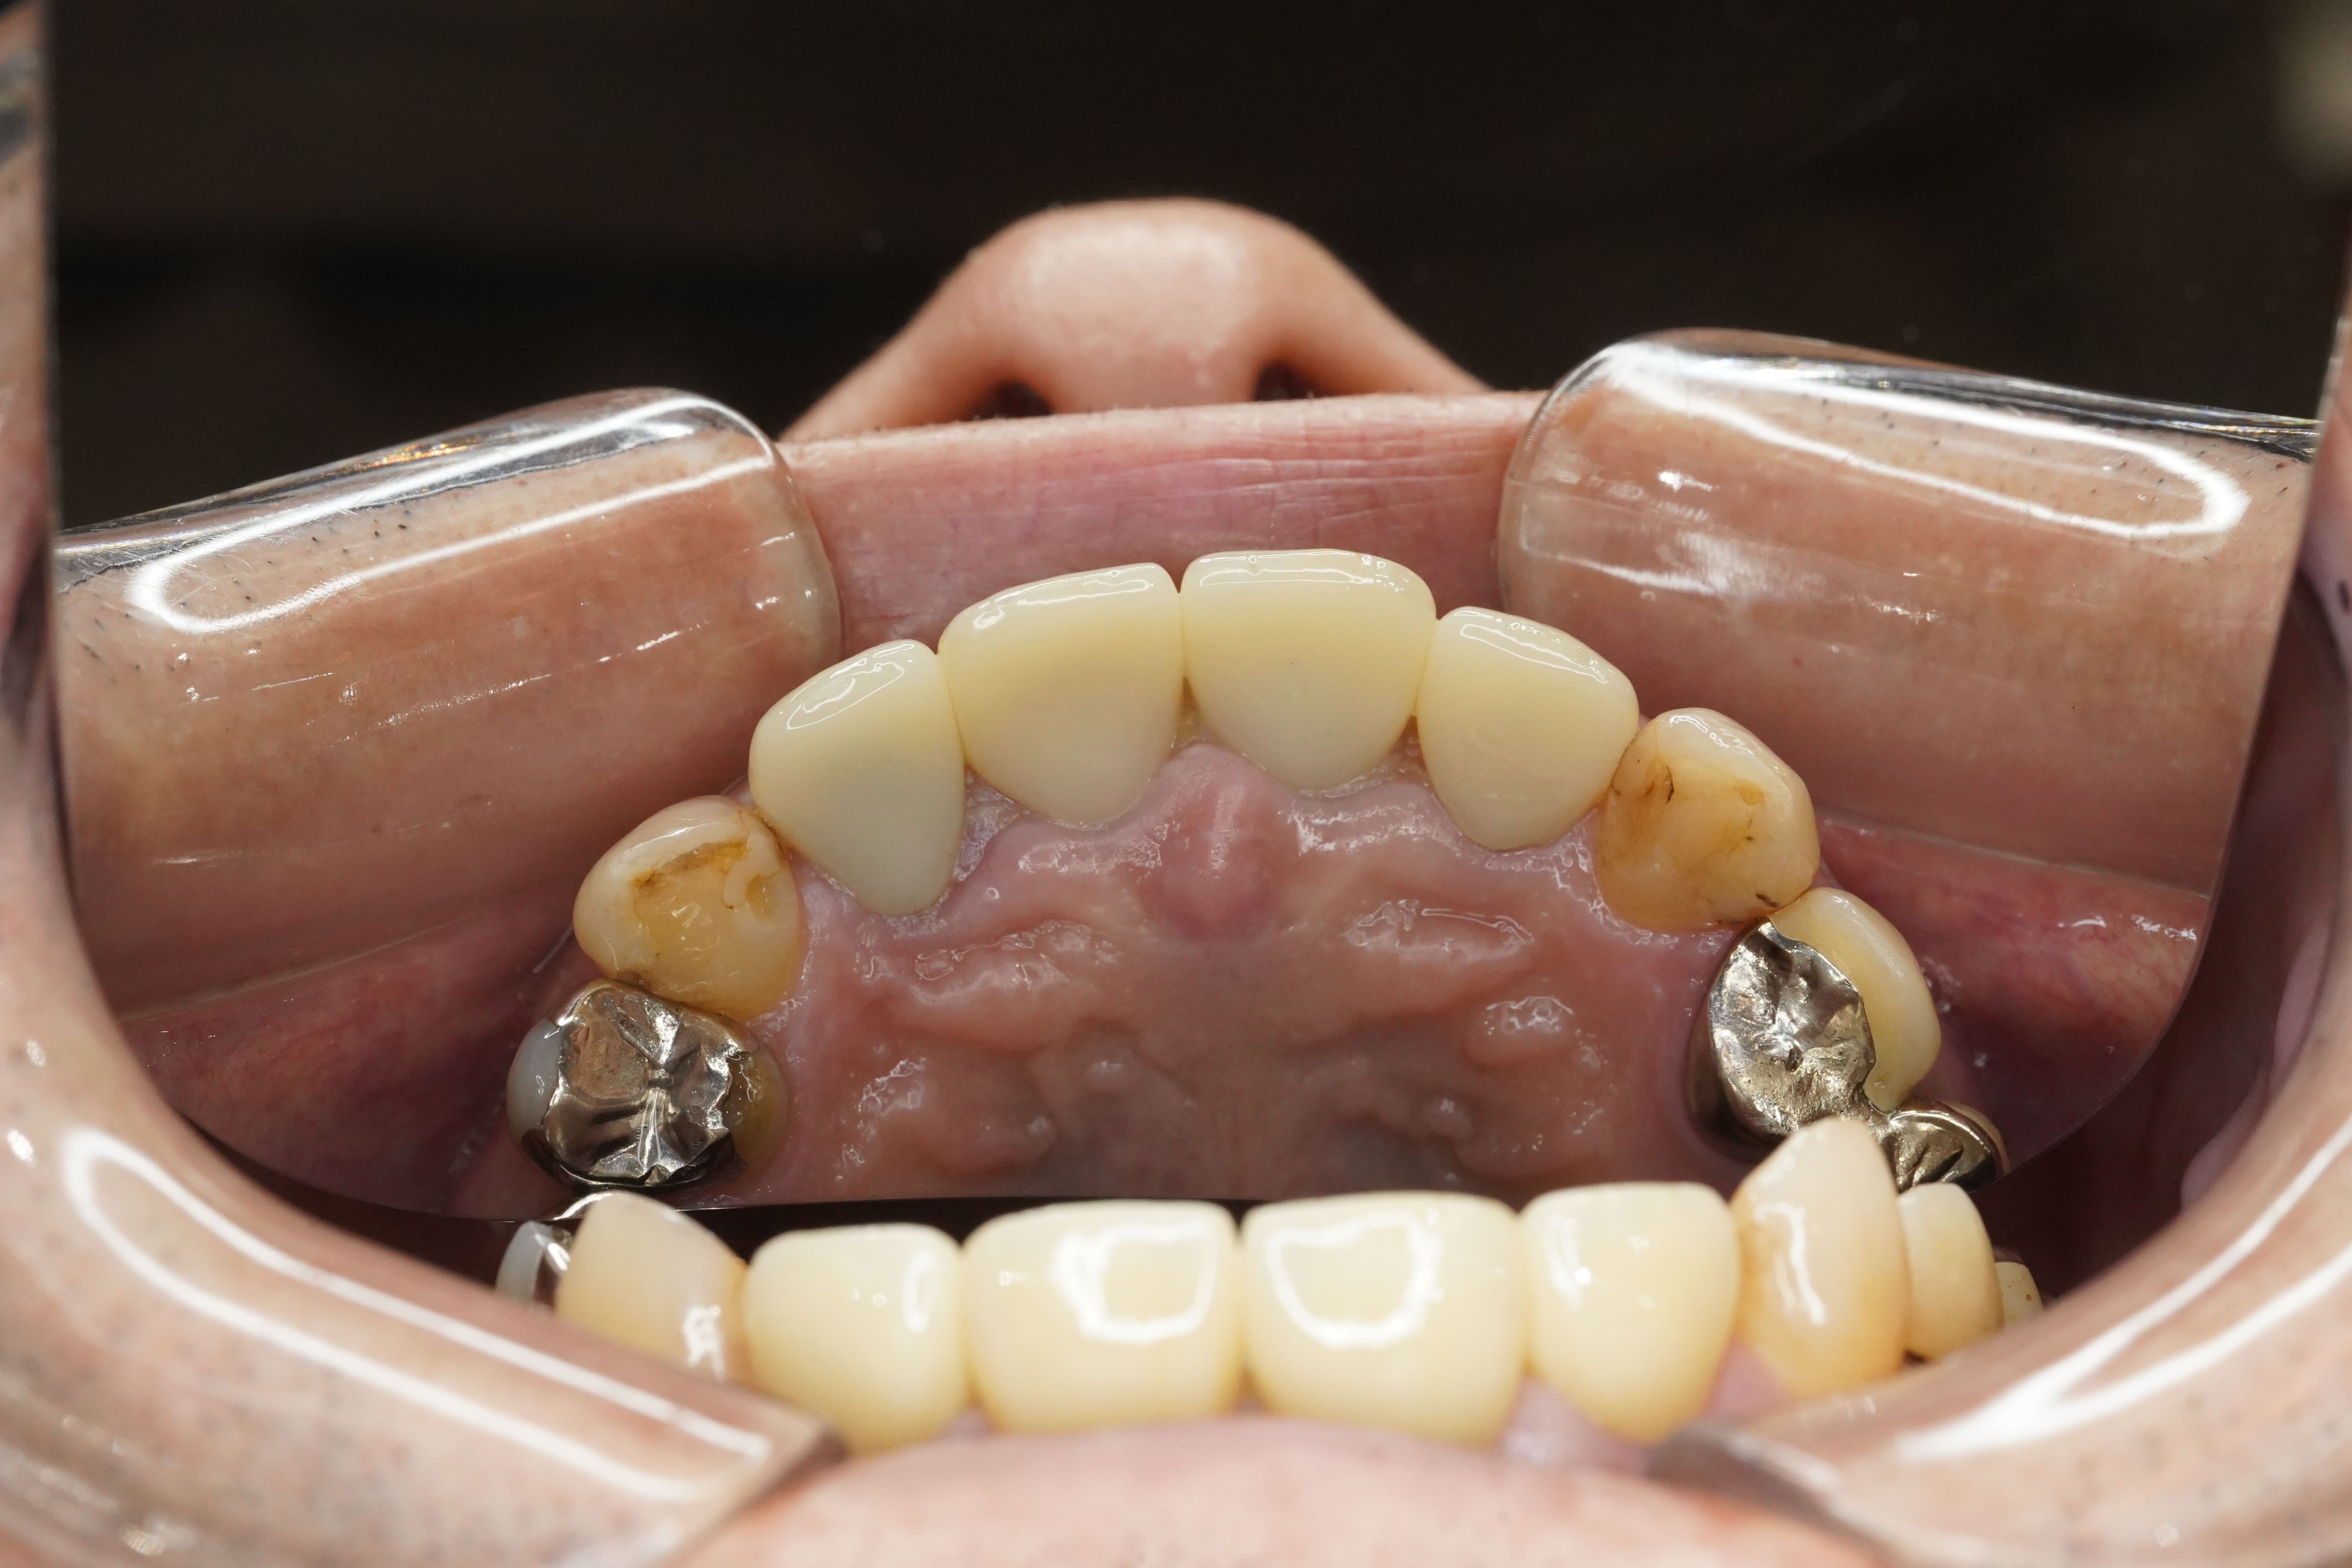

処置後Photo👀✨

補綴物Photo🦷

処置内容➡︎全て分析から、右上側切歯は根尖性歯周があり感染根管治療とファイバーコア、左上側切歯は歯根端切除が行われていたためクラウンのみ、他3本はファイバーコアを立ててクラウン修復になります

審美的にも使用感もご満足いただけてよかったです☺️🦷

🦷治療内容:感染根管治療・ファイバーコア・フルジルコニア

🦷技工所:プロミネント